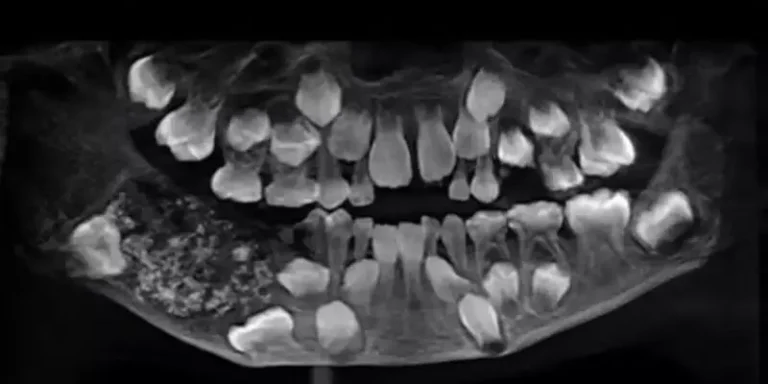

Um menino de 9 anos, com um caso raro conhecido como Odontoma Composto Complexo, chamou atenção de cirurgiões dentistas da Índia. O...